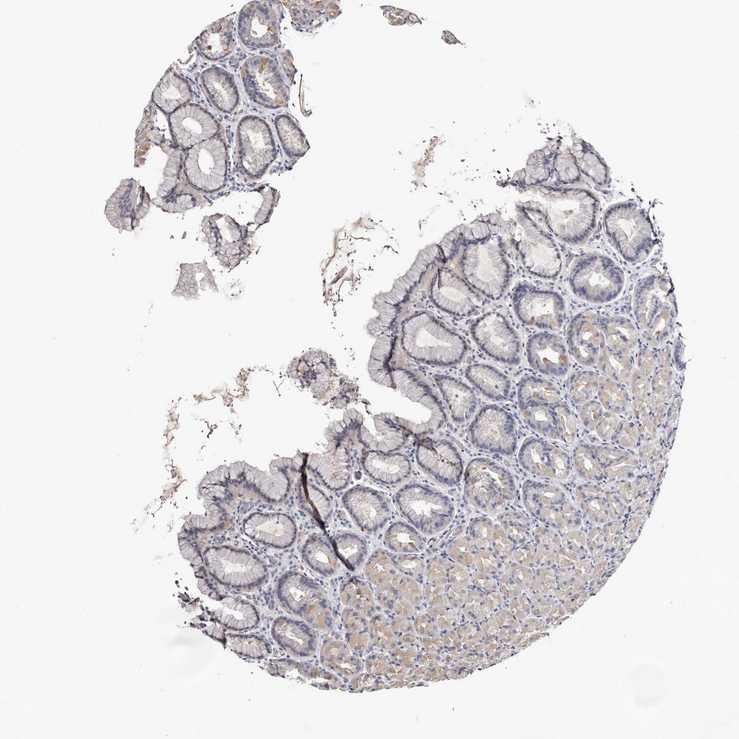

STOMACH 2 - Antibody stainingi

Antibody staining in the annotated cell types in the current human tissue is reported as not detected, low, medium, or high, based on conventional immunohistochemistry profiling in selected tissues. This score is based on the combination of the staining intensity and fraction of stained cells.

Each image is clickable and will lead to virtual microscopy that enables deeper exploration of all samples and also displays staining intensity scores, fraction scores and subcellular localization as well as patient and tissue information for each sample.

Antibody HPA019711Antibody HPA029535

Glandular cells MediumNot detected